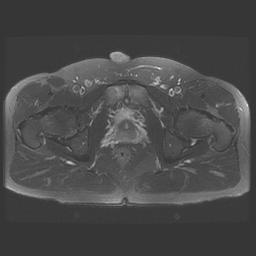

MRI

Can be difficult to see

Is often a clinical diagnosis